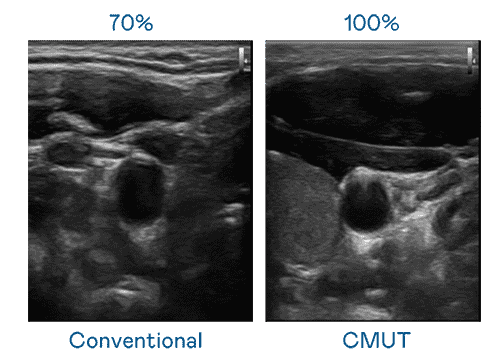

CMUT 技术是一种用电容式微机电元件来产生超音波讯号的技术。。。。与传统 PZT 压电式技术相比,,,CMUT 频宽增加 30%,,,更宽频的超音波讯号让影像解析度大幅提升,,,,是实现高影像品质医疗超音波扫描、、促进精准医疗发展的关键技术。。。。

超音波影像的解析度高低,,,首先取决于探头能发出的讯号频宽。。冰球突破 CMUT 可提供高清晰的超音波讯号,,,,提供高频宽、、高灵敏度、、、影像纹理细节更高的超音波影像,,协助医护人员缩短影像判读时间及利用精准的医疗影像进行诊断。。。。